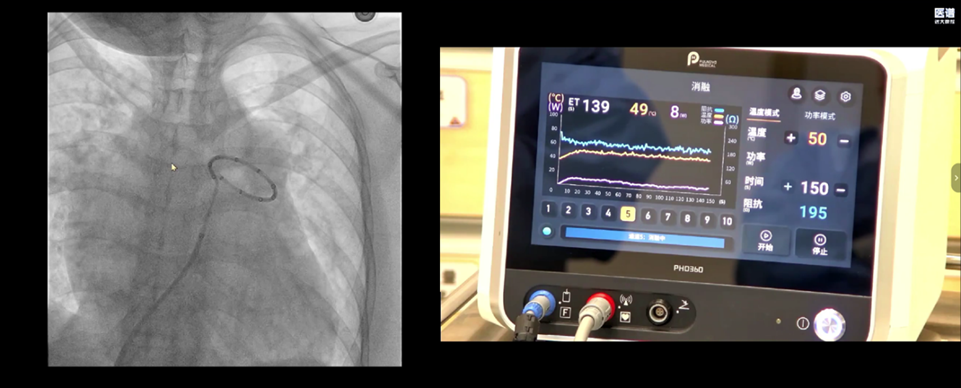

经团队评估,决定行PADN手术。术中行肺动脉造,确认消融靶点位置并测得肺动脉直径为47.3mm,选择50mm的消融导管。

术中,PADN导管经过PFlexi长鞘送至主肺动脉,并行精准消融。

手术过程顺利,术后复测右心导管检查,肺动脉压力、肺血管阻力与心排量均有明显改善,右心负荷得以减轻。PADN通过抑制过度激活的肺动脉交感神经,为肺动脉高压患者提供了新的介入治疗选择。该病例展示了PADN技术在重度肺动脉高压患者中的安全性与可行性,进一步验证了其在中晚期肺高压治疗中的临床应用价值。